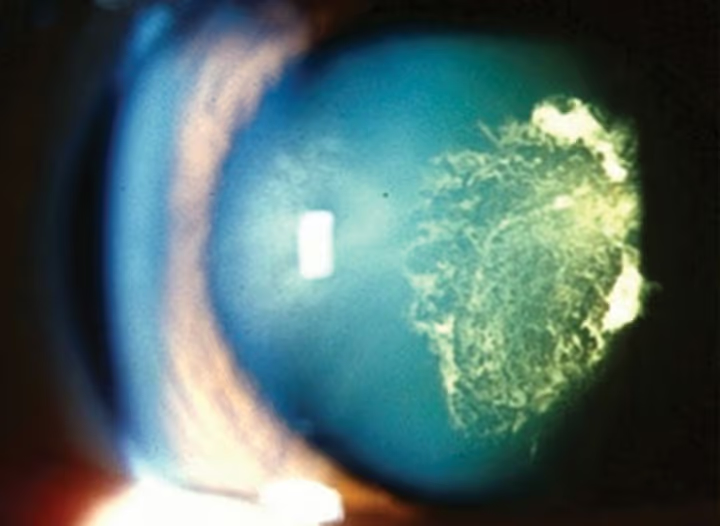

Tipos de catarata

- Catarata traumática: decorrente de trauma ocular (pancada, perfuração, cirurgia).

- Trauma ocular: pancadas, perfurações ou cirurgias prévias.